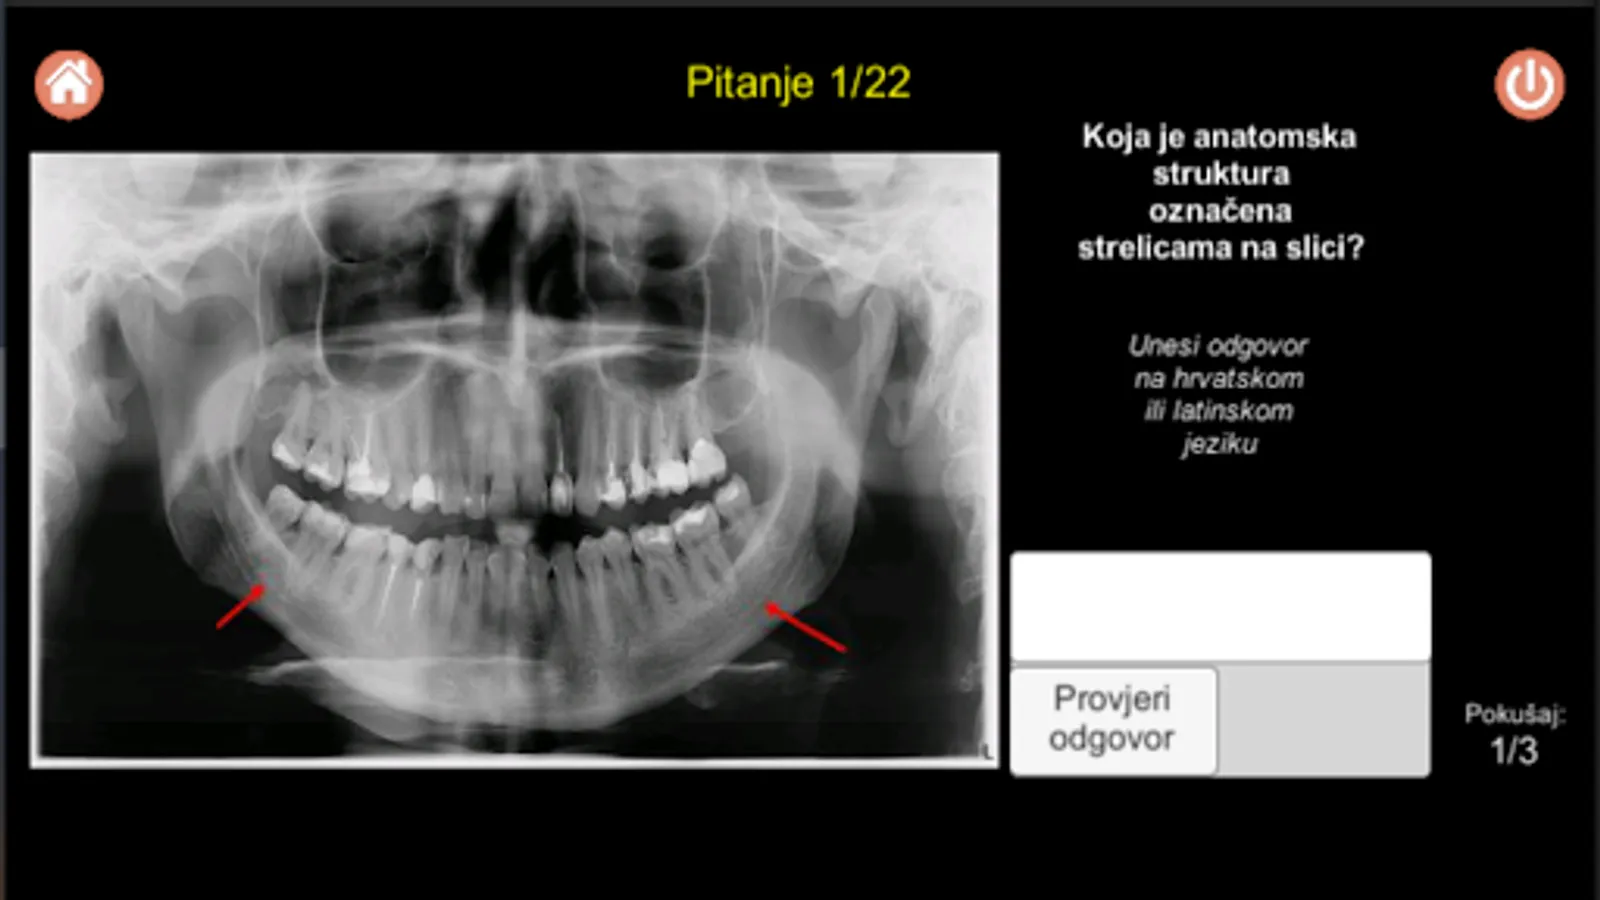

Students are enabled to, in addition to the theoretical part related to endodontic dental treatment, through a knowledge quiz composed of different types of questions and possible answers (eg typing answers, selecting offered answers such as correct / incorrect or selecting a tooth by pressing a specific tooth / teeth in the displayed image of the teeth on the screen, etc.), in a very clear and attractive way gain insight into various issues in the field of endodontics and the application of endodontic dental treatment. In addition, through this software solution, students are given the opportunity to get acquainted with EndoActivator (sound-activated channel flushing) and SWEEPS technique (laser-activated flush), where, in addition to the theoretical part, video materials are implemented in this software solution.